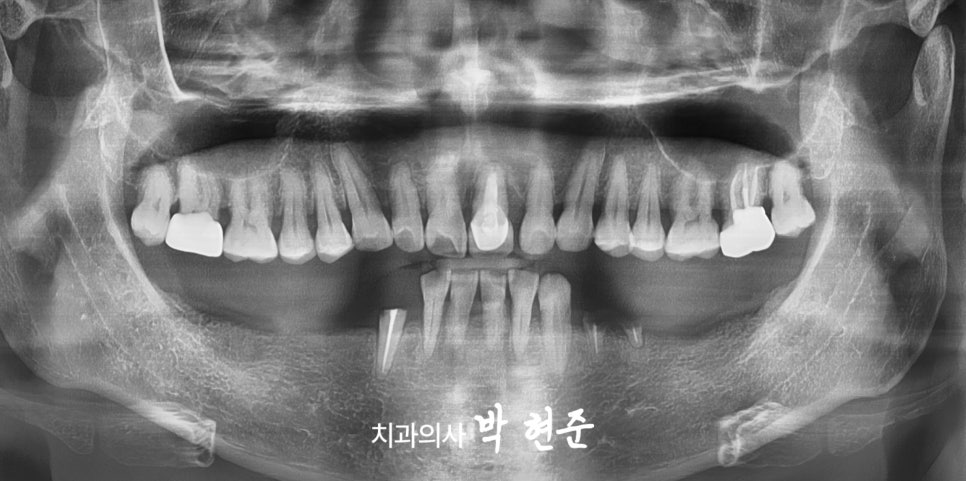

예시 구강 사진을 관찰해보면

다수의 상실된 치아가 발견됩니다.

이를 통해 평소 틀니를 사용한 것을

예상할 수 있습니다.

또한, 치아 뿌리만 남은 채 파절된 곳도

발견됩니다.